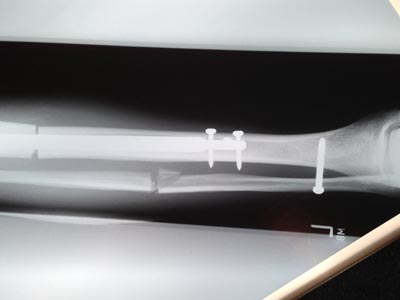

Face à une demande croissante, nous avons depuis 2009 très largement renforcé notre activité médicale.

L'étroite collaboration entretenue avec nos partenaires ainsi que la maitrise des exigences de ce secteur (Normes, Matériaux...) nous permettent aujourd'hui de développer des dispositifs innovants.